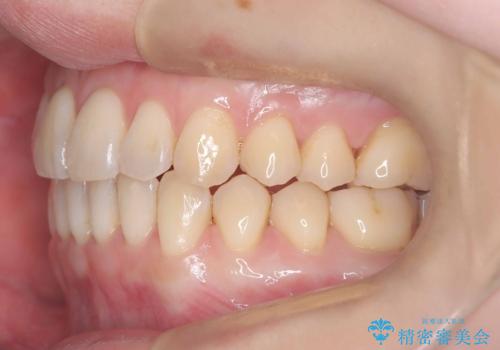

- 「下の前歯が斜めになっている」を主訴に来院された患者様です。

下顎前歯に叢生があり、右上2は反対咬合の状態でした。

下顎前歯の叢生がとれ右上2の反対咬合も改善し患者様にも満足していただけました。治療期間は1年~1年半を見込んでいましたが、患者様の協力もあり10か月で矯正を終えることが出来ました。